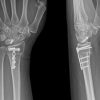

An anteroposterior and lateral plain radiograph of pelvis with both hips showed a left hip SCFE with still open proximal femoral physis (Fig. 1a, b). In addition, the pelvis x-ray showed a bone age of Risser stage 0 and open triradiate cartilage. In view of the clinical and radiological signs, a detailed endocrine workup was carried out by the pediatric endocrine team. Blood examination showed normal triiodothyronine [T3] (1.37 ng/ml; normal: 0.5–1.6), low thyroxin [T4] (3.7 ng/ml; normal: 4.9–11.6), and elevated thyroid-stimulating hormone [TSH] (45.79 ng/ml; normal: 0.4–6.16). The rest of the laboratory parameters including renal function tests, growth hormone, testosterone, and cortisol were within normal limits. The patient was diagnosed with Primary hypothyroidism. He was commenced on levothyroxine tablet 100 mcg once a day for 5 days in a week and a half tablet for 2 days a week. After 1.5 months of treatment, normal T4 and TSH levels were achieved.

The patient was planned for surgery urgently due to the SCFE being unstable. The positional reduction was achieved by gentle positioning of the patient on the traction table. Although reduction was not complete, no attempts at closed reduction were made and in-situ fixation was carried out with two 6.5 mm partially threaded Cancellous Cannulated screws, ensuring the screws remained perpendicular to the physis (Fig. 2a, b).